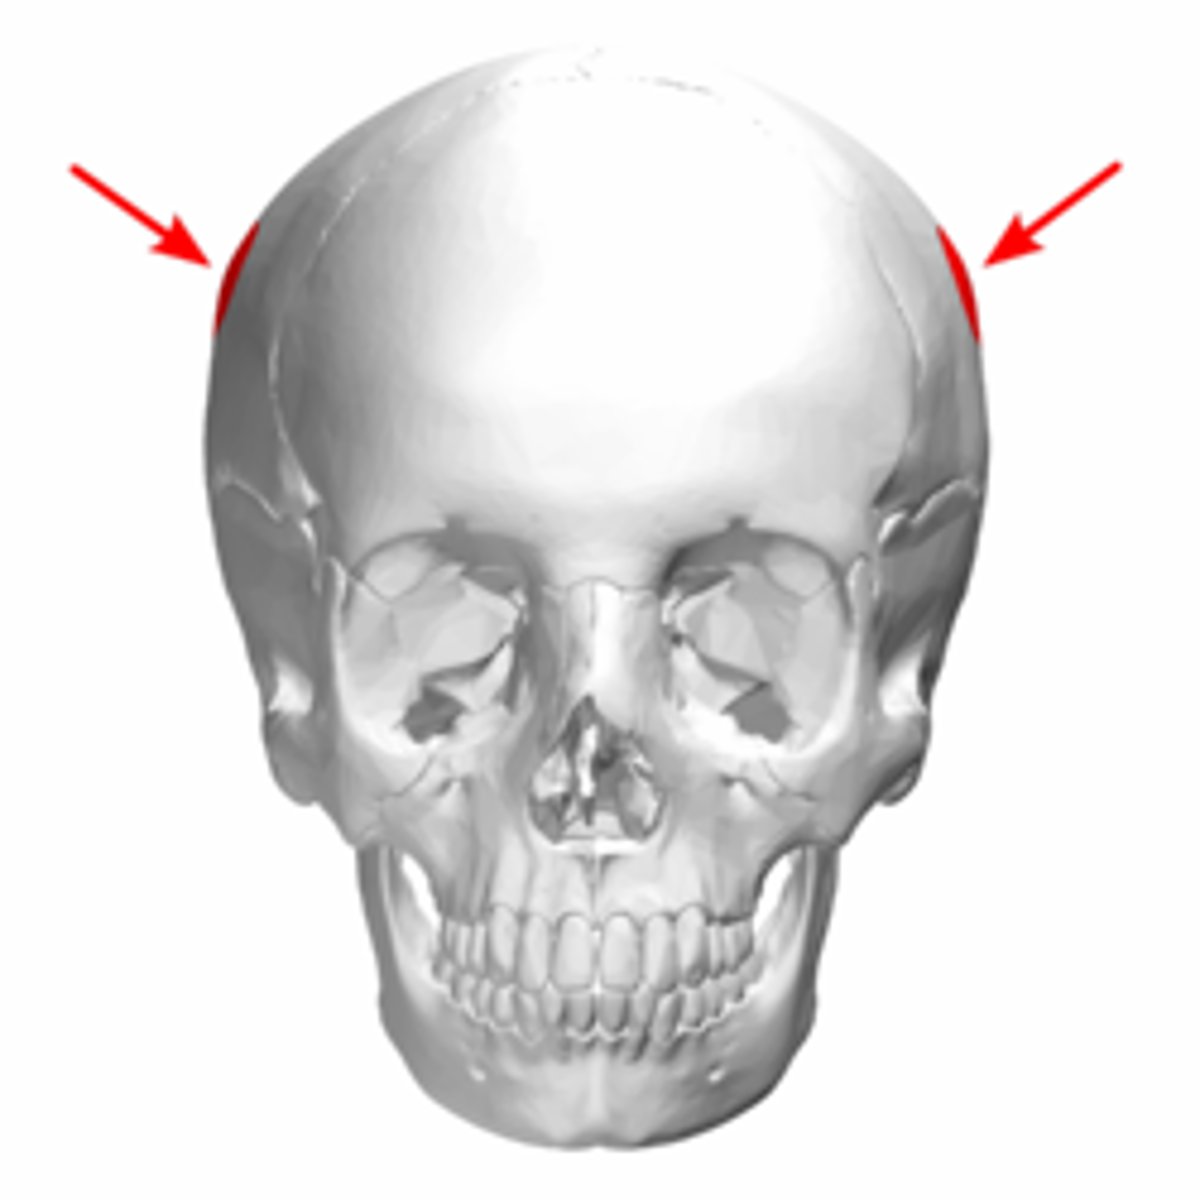

parietal eminence